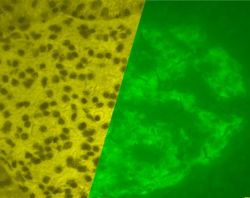

Mouse islet immunostained for pancreatic polypeptide

Mouse islet immunostained for pancreatic polypeptide Mouse islet immunostained for insulin

Mouse islet immunostained for insulin Mouse islet immunostained for glucagon

Mouse islet immunostained for glucagon Illustration of dog pancreas. 250x.